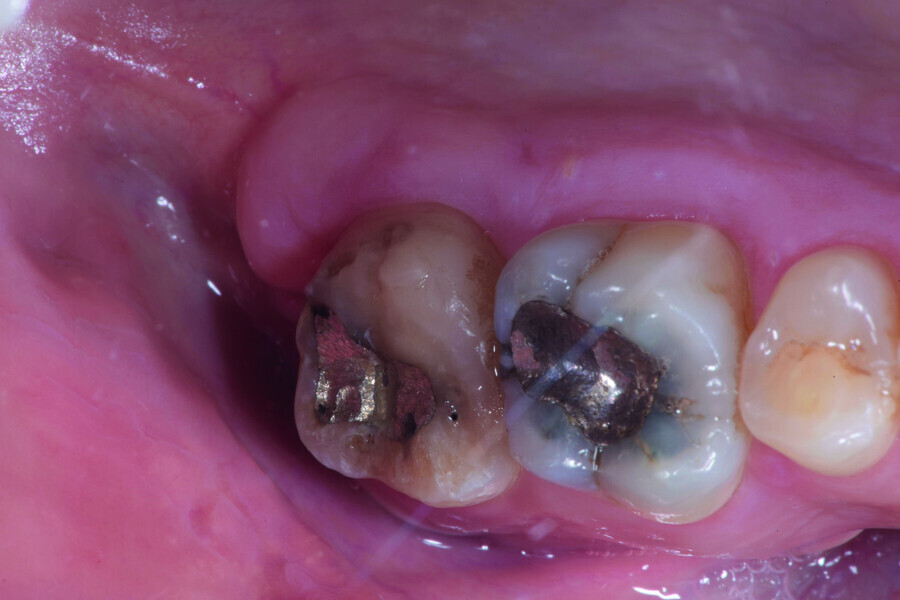

Fig. 2: Pre-op facial view.